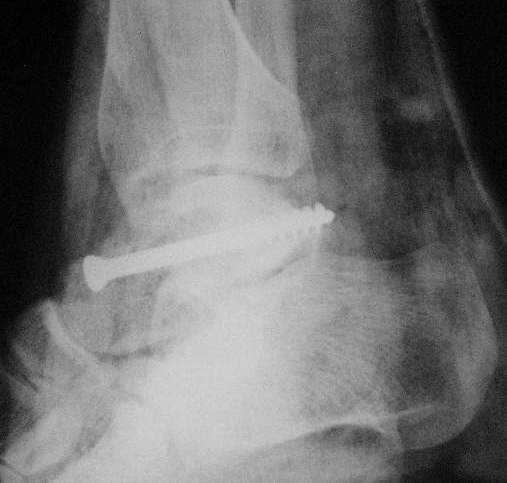

Переломовывих тарана с повреждением медиальной стороны. Через 4 часа после поступления проведена репозиция и фиксация тарана после Irrigation&Debridment. Частичное несращение медиальной лодыжки не беспокоит, вернулся к активному образу жизни. Полная нагрузка разрешена через 11 недель. Финальные снимки через 11 месяцев.